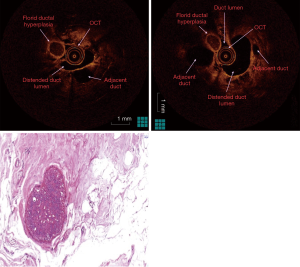

The fluid-yielding duct of the prophylactic mastectomy specimen was scanned with OCT in order to obtain abnormal imaging. Cross-sectional OCT images acquired from the ductal lining showed normal (sub-)epithelial layers proximally and round undefined lesion adjacent to the distended duct distally (Figures 2,3). Ductoscopy failed to show the lesion acquired by OCT. The lesion was 2.5 cm away from the nipple with a diameter of 1 mm, which was measured during OCT scanning. The histopathology revealed a florid ductal hyperplasia (FDH), which causes obliteration in the ductal lumen (Figure 3). This is the first time in the literature an OCT imaging of an FDH in a breast duct was acquired endoscopically or intraductally. The impact of this imaging case was the unique discovery of a high-risk lesion by intraductal OCT, which could not be detected by any conventional imaging.

To our knowledge, no study has been published in the literature regarding real-time cross-sectional imaging of ductal space by OCT, which enters via nipple orifices. Since the milking ducts are very narrow to enter, only mini-endoscopic instruments such as ductoscopy have been developed to acquire images of pathologic lesions (7). OCT studies on breast include only the analysis of OCT to evaluate surgical margins of lumpectomy specimens (8,9). Furthermore, the OCTs used in those studies did not include a catheter aid to acquire cross-sectional images via natural orifice. However, we used a catheter-based OCT to enter the natural duct orifices in order to achieve direct images from epithelium and layers underneath. Intraductal OCT were able to show ductal epithelium, layers and cavities as cross-sectional images similar to standard hematoxylin & eosin slides. The distention of the duct by saline made the OCT procedure more efficient than the use of the catheter in shrunken ex vivo ducts. The distention did not upgrade resolution, however, made the images of the ductal epithelial layer, lumen, and lesion more clear and distinguishable than the images acquired in shrunken ducts. The use of OCT catheter in vivo in future studies would also need saline infusion and distention from our experience on ductoscopy used for PND which is very similar technically (2-4).

Recently, Yemul et al. (13) assessed mastectomy and breast-conserving surgery specimens from 26 women who were imaged with a handheld OCT probe. Histology slides corresponding to the OCT image region were digitally photographed. OCT and histology images from the same region were paired by selecting the best structural matches. In total, 2,880 OCT images were acquired from 26 breast specimens, and 48 matching OCT-histology image pairs were identified. Differentiation between pathologies was achieved by considering feature boundaries, interior appearance, posterior shadowing or enhancement, and overall morphologic patterns. The results indicate that OCT can be used to identify and distinguish between benign and malignant features in human breast tissue. In our study, round lesion approximately 1mm with a border were found, which caused complete obstruction in the duct shown as hyporeflective interiors and well-circumscribed boundary architecture with distinct edges. These architectural findings of FDH in our study are similar to the findings of Yemul et al. as a hyporeflective interior, less distinct boundaries for hyperplastic ducts.